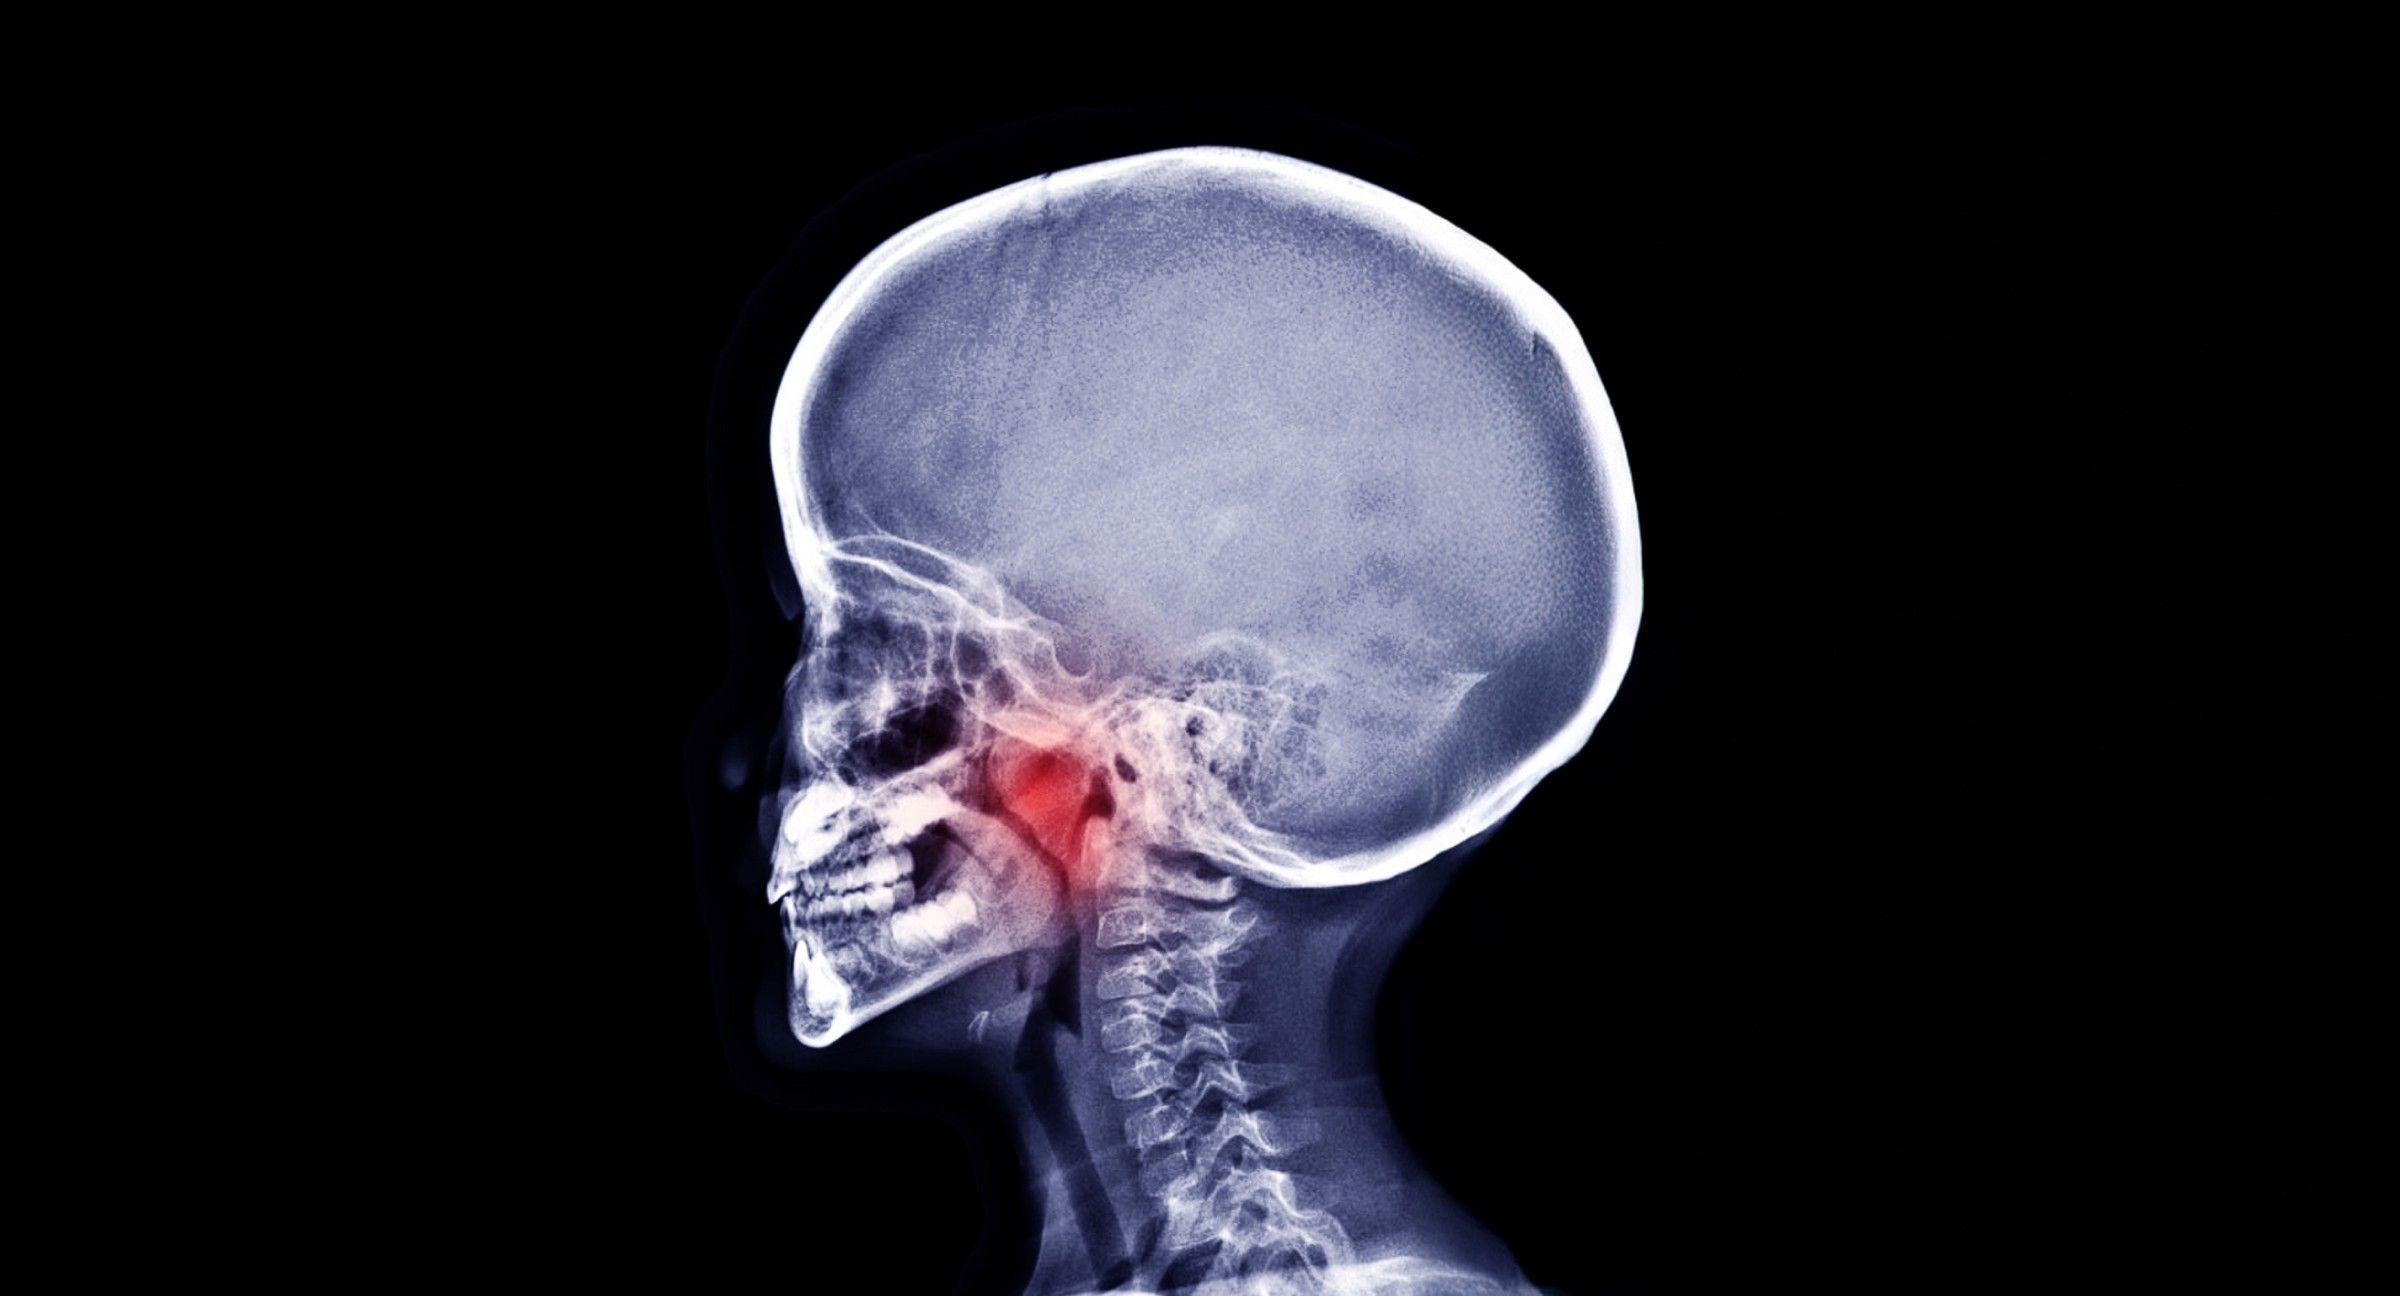

Unlike traditional orthodontics, which focuses mainly on straightening teeth and fixing bite issues, airway orthodontics takes a comprehensive approach to dental health.

Instead of deferring minor health issues until adulthood, we tackle them early, examining how your child’s jaw development, breathing patterns, and general oral health impact their overall well-being.

During our initial consultation, we might evaluate your child’s breathing patterns, focusing on tongue position, swallowing habits, and jaw growth patterns. We do this early in life to detect minor health and dental issues before they turn into sleep apnea, mouth breathing, or other concerns.